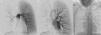

Arteriografía pulmonar en la que se aprecia hipoplasia de arteria pulmonar derecha que aporta escasa perfusión y, prácticamente, solo para el lóbulo superior (A), en la que no se evidencia drenaje venoso derecho (B). Arteriografía de aorta torácica que muestra arteria bronquial irregular y tortuosa con origen en cara anterior y superior de aorta torácica descendente (C).

Presentamos el caso de una mujer de 19 años, fumadora de 8 paquetes-año, y consumidora habitual de cannabis, con antecedentes de bronquitis grave en la infancia e infecciones respiratorias frecuentes. Consultó por episodios de tos con expectoración hemoptoica desde los 15 años, que al principio eran esporádicos, pero que en los últimos meses se habían hecho más frecuentes, ocurriendo a veces cada 48h. A la exploración destacaba la disminución del murmullo vesicular en hemitórax derecho y la presencia de acropaquias. La radiografía de tórax mostró pérdida de volumen de pulmón derecho y atenuación del hilio derecho. En la tomografía computarizada (TC) no se identificaron venas pulmonares derechas y el pulmón afecto presentaba un aumento difuso de su densidad. El estudio de resonancia magnética (RM) cardiaca descartó la existencia de cardiopatías asociadas, y la ecocardiografía, la presencia de hipertensión pulmonar. Se realizó arteriografía pulmonar (fig. 1A y B) en la que se apreció hipoplasia de la arteria pulmonar derecha y ausencia de retorno venoso pulmonar derecho. La arteriografía de aorta torácica (fig. 1C) evidenció hipertrofia de arteria bronquial derecha con origen en aorta descendente. Las pruebas de función pulmonar fueron: FEV1: 2.040 (75,5%), FVC: 2.800 (90,1%) y DLCOc SB: 69,3%. En la fibrobroncoscopia se apreciaron varices en tráquea distal e inicio del bronquio principal derecho. Considerando los hallazgos previos, se optó por el tratamiento quirúrgico de la paciente. Fue sometida a neumonectomía derecha. El postoperatorio inmediato transcurrió sin incidencias y la paciente se encuentra asintomática en el momento actual.